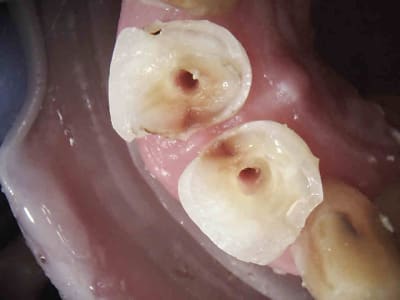

Tiens un cas s'approchant du tiens Chicot...comme je suis mauvais en Endo, j'essaye d'en faire le moins possible.

J'ai gardé vivant ce que je pouvais.

Le cas à 3 ans... RAS, j'ai vu la patiente il y a 2 mois.